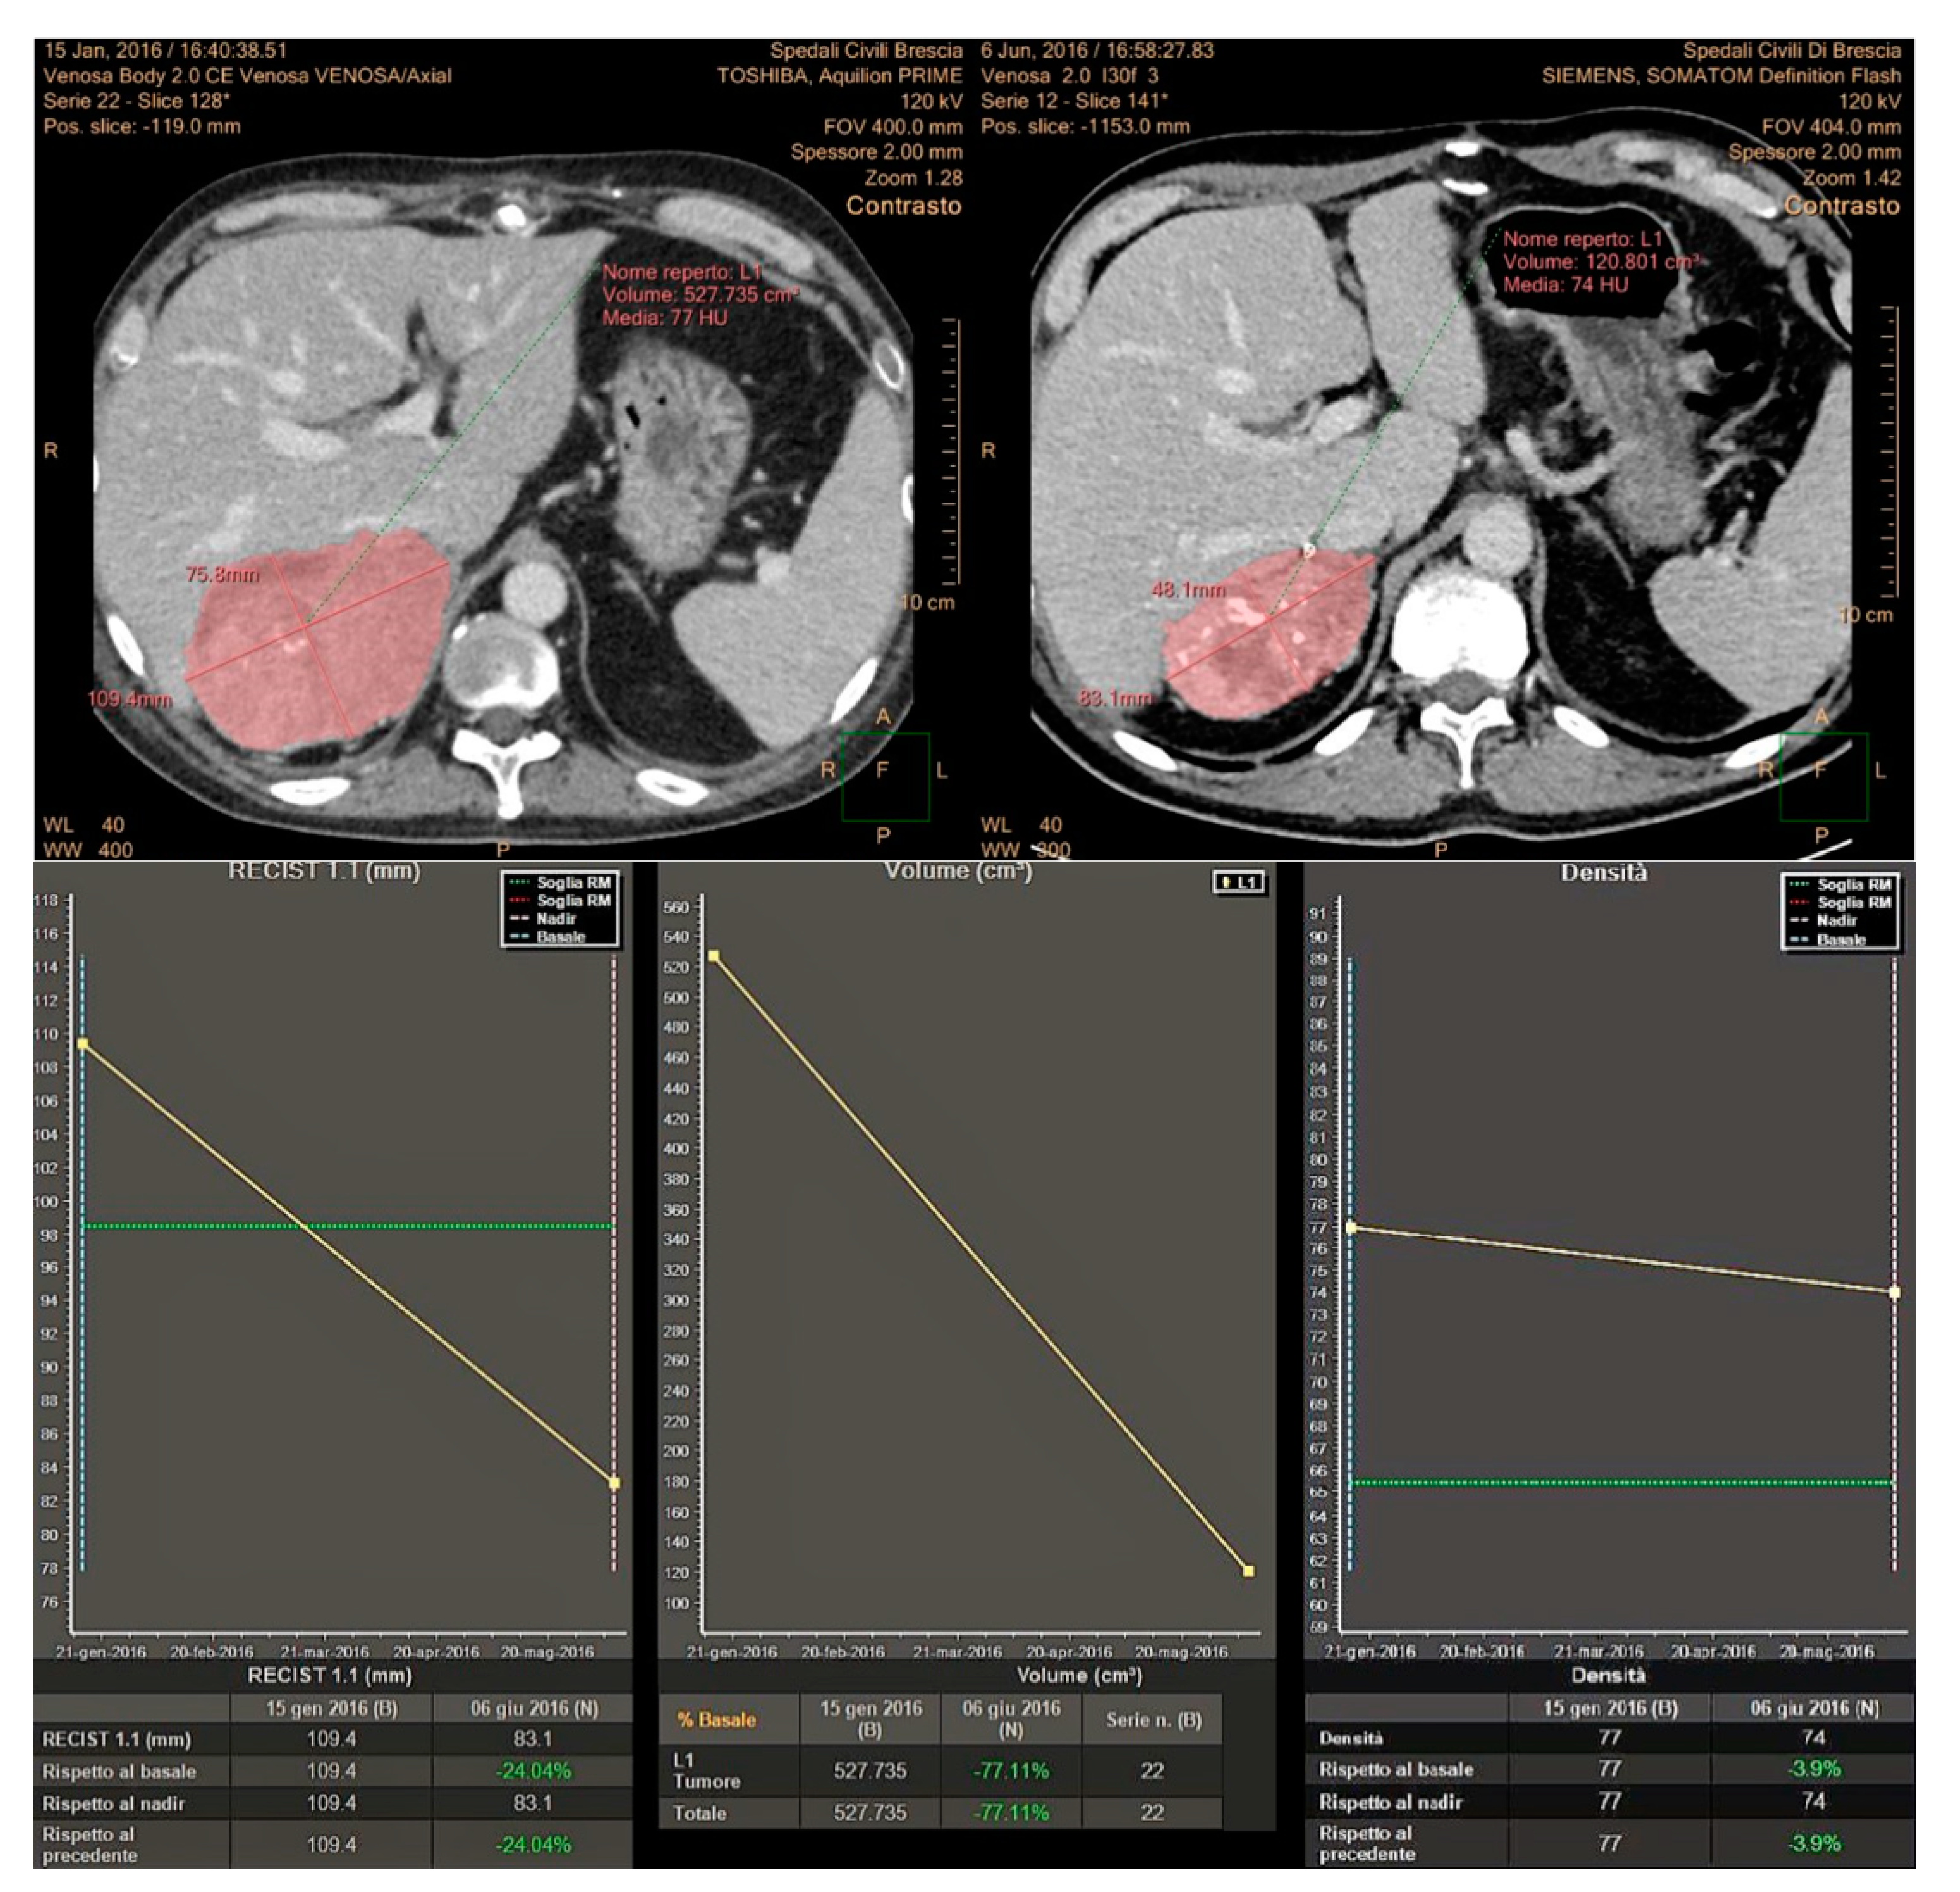

In this study, we have prospectively evaluated disease response at CT imaging of advanced/metastatic ACC patients submitted to EDP-M regimen, adopting RECIST 1.1, Choi and volumetric criteria (Figure 6). Partial response assessed by each criterium significantly correlated with patient outcome, both in terms of PFS and OS. However, the concordance among these criteria in defining the disease partial response was observed in 8 patients (23.5%), while in 7 patients (20.5%) the response observed with one criterion was not confirmed by one or 2 other criteria. We therefore adopted a comprehensive approach, considering as responders all patients showing a disease response with at least one criterion. Using this definition, the proportion of responders increased from 23.5% to 44% with respect to standard RECIST 1.1, and responding patients maintained a better PFS and OS than patients with SD and PD. We subsequently evaluated the prognostic effect of the response recognized by all three criteria than discordant response between criteria and disease stabilization or progression. The results showed that patients in whom the response was agreed upon by the three criteria obtained the best prognosis in terms of PFS and OS. Patients, whose response was identified by one or two criteria, but not by all the three obtained a better survival, although not a significant advantage in terms of PFS than patients with SD and PD.

Figure 6. Concordance of the three response criteria in the assessment of a primary metastatic ACC, with planar dimensions changes (RECIST 1.1), tumor volume and tumor size/attenuation (according to Choi).

Two experienced Radiologists (R.A., M.D.T.) performed 3D semiautomatic segmentation of target lesions on the baseline examination and on the first CT after chemotherapy, using a dedicated software (Multi-Modality Tumor Tracking, IntelliSpace Philips Portal, version 10, Philips Healthcare, Best, The Netherlands). After segmentation, the software automatically compares the examinations in terms of the long and short axis, lesion volume and CT attenuation. Furthermore, aside from the calculation of the percentages of variations, the software provides a chart where relative changes of the analyzed tumor characteristics between multiple examinations are immediately evident. In this study, we evaluated tumor response considering the sum of the longest diameter of all lesions (RECIST 1.1 criteria), the presence of attenuation changes at CT (CHOI) and volume changes after therapies (Figure 8).